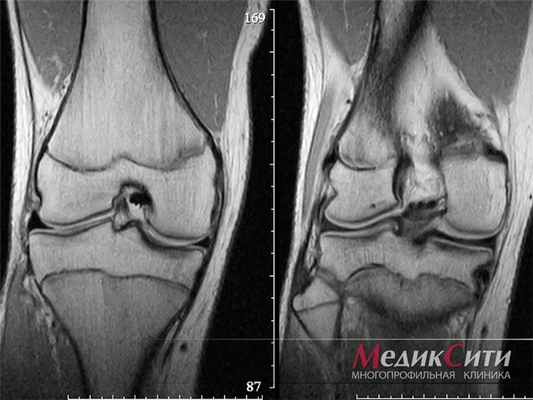

МРТ колена ребенка: норма